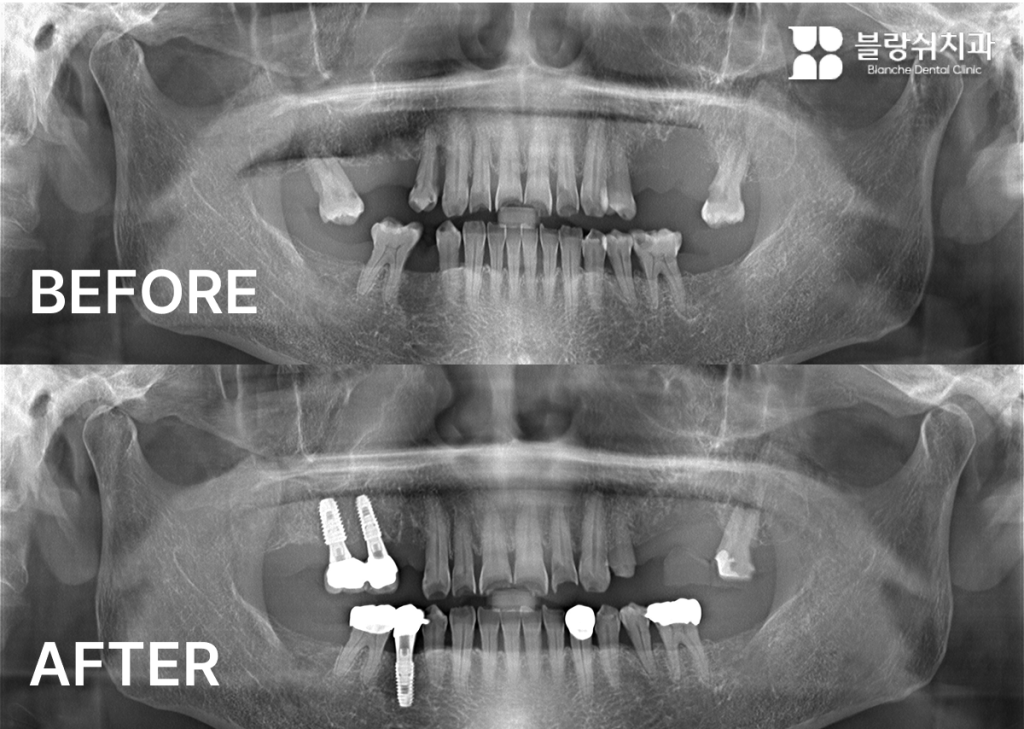

이 환자분은 치과 공포증과 당뇨로 인해 임플란트 시술을 오랫동안 미뤄오셨습니다. 당뇨 환자는 치유가 더디기 때문에 더욱 세심한 접근이 필요한데, 수면진료와 무절개 방식으로 시술해 회복 부담을 최소화했습니다. 눈을 감았다 떴을 때 치료가 이미 끝나 있었다며, 진작 올걸 하셨다고 하셨습니다.